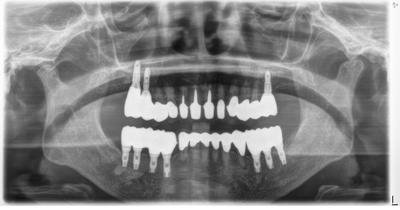

HOME > ブログ 一覧 > インプラント包括ケース 2021.03.23インプラント包括ケース 下顎は術後15年、上顎は7年、鋭意メインテナンス中。 8年の治療時期のズレは、治療コンセプト、マテリアルの進化等様々な差があるが、問題はない。 でも、肝心なことは良好な予後=患者さんの利益。 Recent Entries アライナー矯正(インビザライン、シュアスマイル)費用を2023年 1月から改訂させていただきます(01/09) 本年もよろしくお願いいたします(01/02) 年始の診療について(01/01) 新しいWEBへ移行、年末年始の診療のお知らせ(12/29) ダラダラ根管治療行っても治らないという事(12/21) Category その他の治療(126) インビザライン・矯正(52) インプラント治療(216) ホワイトニング(47) メインテナンス(21) 包括診療(95) 医院からのお知らせ(249) 審美治療(128) 日々雑感(283) 根管治療(100) 歯周病治療(90) 矯正(73) 補綴治療(45) 補綴治療カテゴリを追加(1) 診療全般(44) Archive 2023年1月(3) 2022年12月(6) 2022年11月(14) 2022年10月(6) 2022年9月(8) 2022年8月(7) 2022年7月(13) 2022年6月(8) 2022年5月(7) 2022年4月(7) 2022年3月(6) 2022年2月(7)